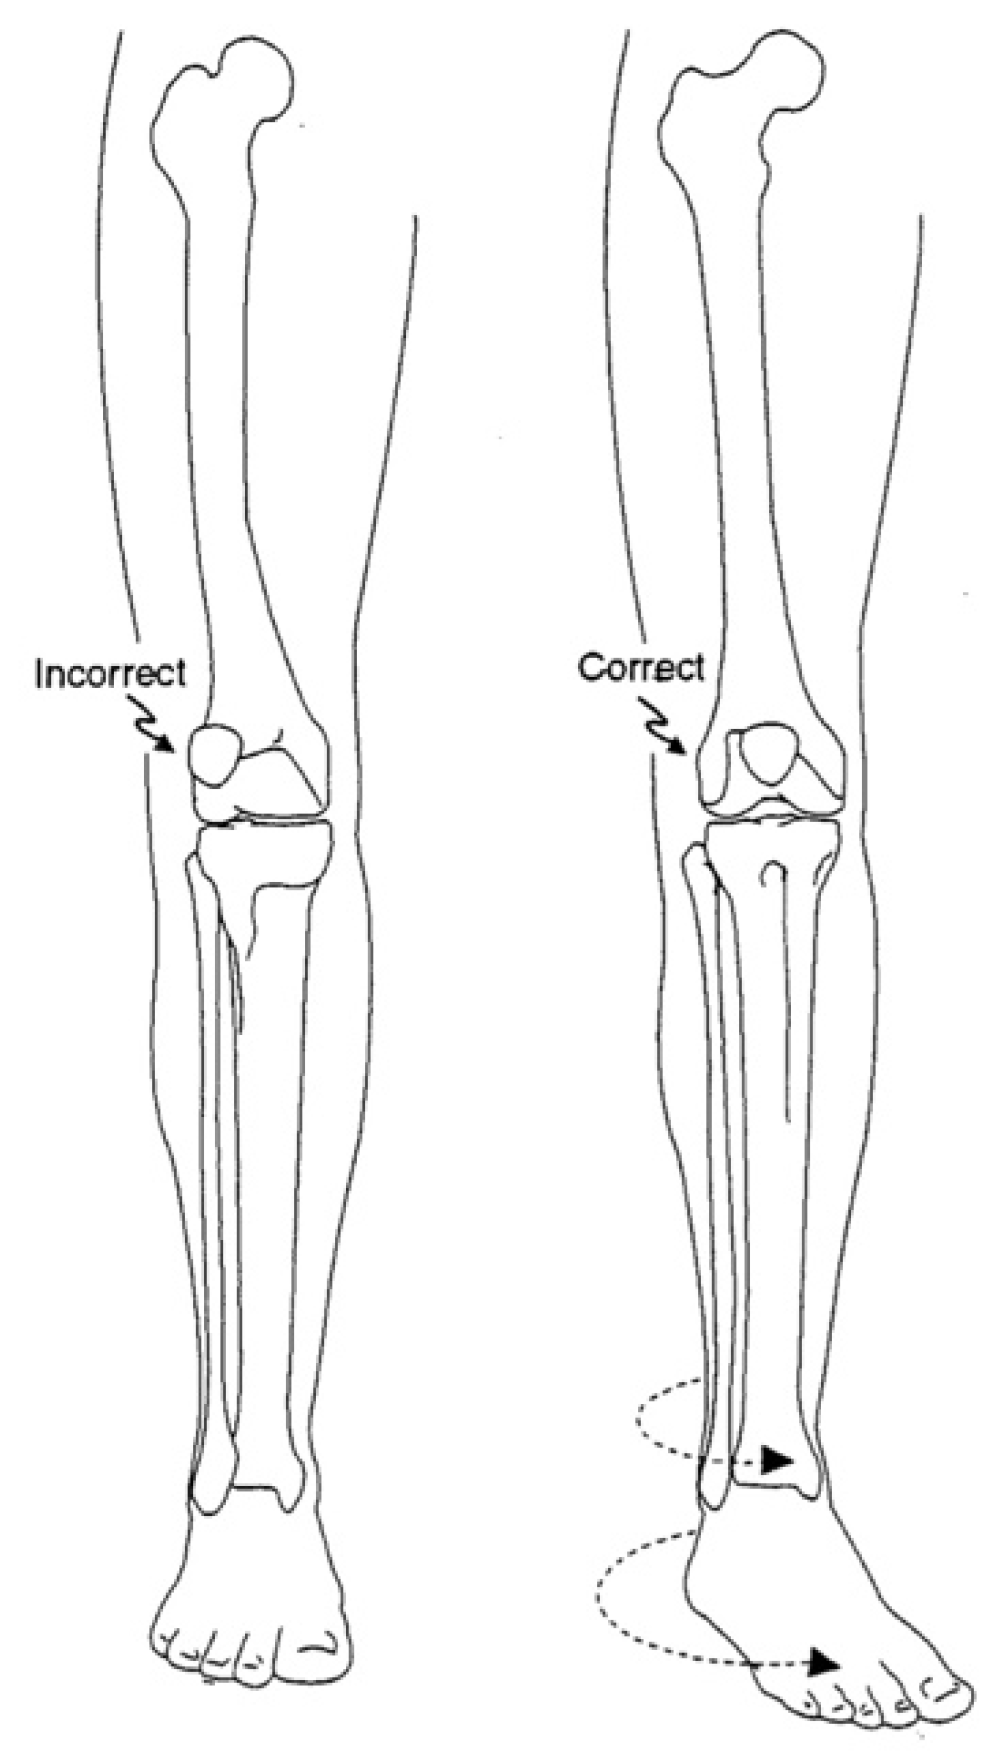

3. ITV Differential Diagnosis and Clinical Features

4. Radiographic Imaging

5. Radiographic Analysis